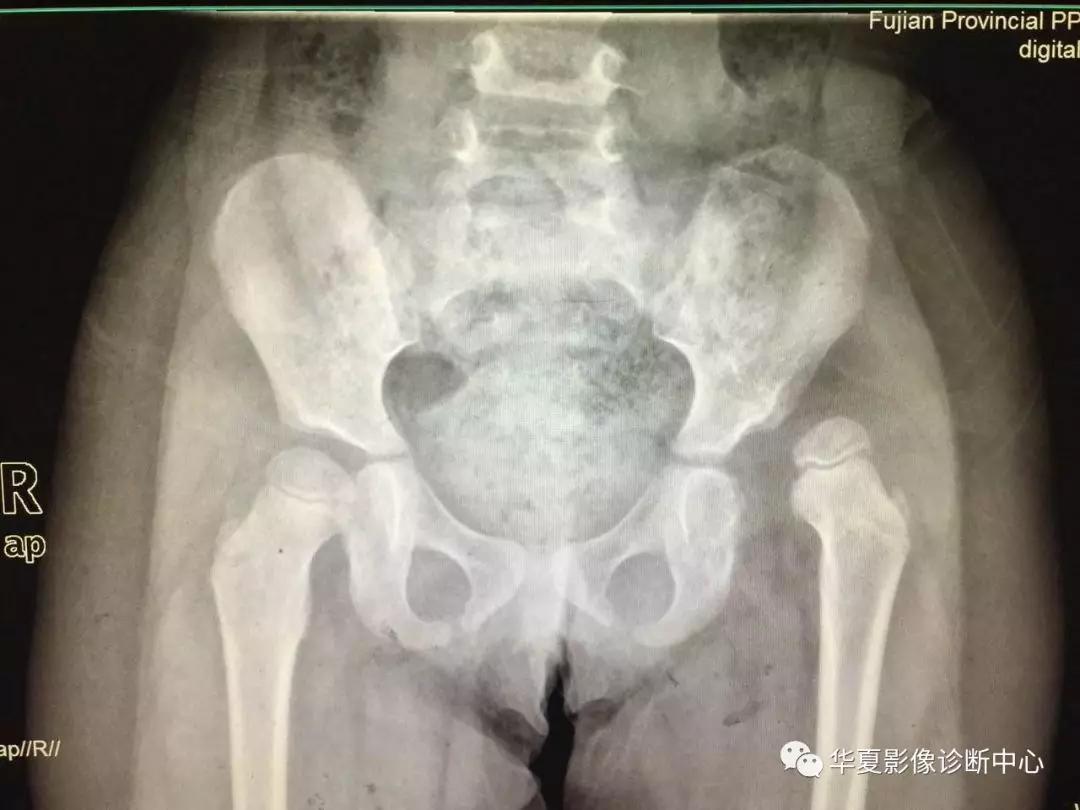

上图:骨盆正位

2.骨盆平片测量法

如图所示两侧髋臼Y形软骨连成为Hilg-eneriner线,简称为H线,股骨上端距H线之距离为上方间隙。股骨上端鸟嘴距坐骨支外缘为内侧间隙,正常均值上方间隙为9.5mm,内侧间隙为4.3mm。若上方间隙小于8.5mm,内侧间隙大于5.1mm应怀疑髋关节脱位。若上方间隙小于7.5mm,内侧间隙大于6.1mm可诊断为髋关节脱位,此法简易可靠。

3.Perkin象限

当股骨头骨骺核出现后可利用Perkin象限,即两侧髋臼中心连一直线称为H线,再从髋臼外缘向H线做一垂线(P),将髋关节划分为四个象限,正常股骨头骨骺位于内下象限内。若在外下象限为半脱位,在外上象限为全脱位。

新生儿正常股骨上端鸟嘴状突起位于内下象限内。若在外下象限为半脱位,在外上象限为全脱位。